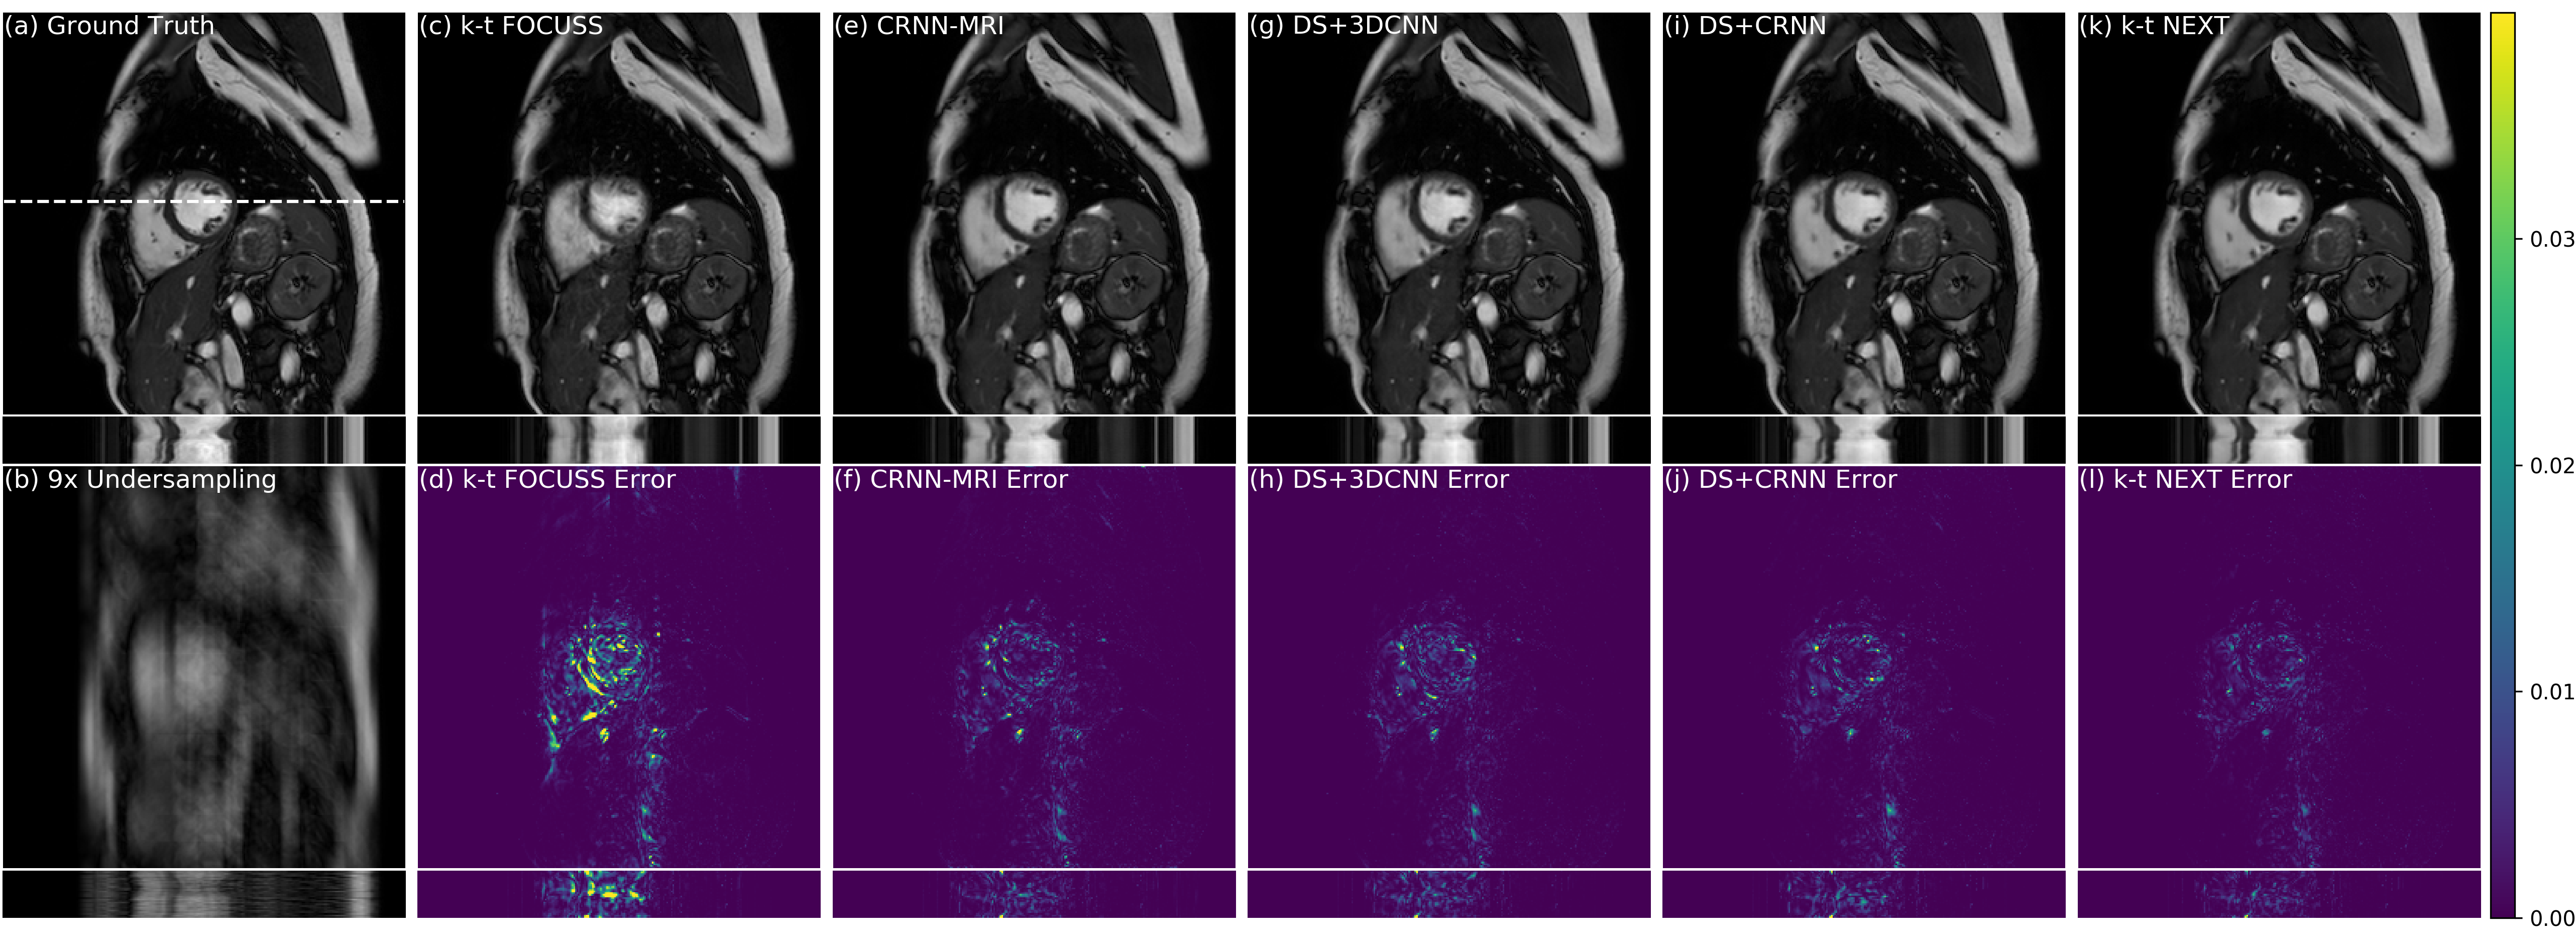

Additionally, we compared the qualitative results on 9Γ—9\times undersampled data in Fig. 2, where it shows the reconstructed images along both spatial and temporal dimensions, as well as their corresponding error maps. It can be observed that our proposed model can faithfully recover the images with smaller errors especially around dynamic regions compared with other baseline methods. In particular, kπ‘˜k-t𝑑t NEXT produced visually sharper images than DS methods. This is reflected by the fact that, in contrast to DS approaches which fill in kπ‘˜k-space data from neighboring frames and therefore could possibly generate averaged and smooth images, kπ‘˜k-t𝑑t NEXT directly estimates the missing data in xπ‘₯x-f𝑓f space. A visualisation of xπ‘₯x-f𝑓f reconstruction is also presented in Fig. 3, where it displays the reconstructed xπ‘₯x-f𝑓f image and its error map in comparison to the input aliased data. It can be observed that the aliasing artefacts were largely removed and the undersampled data were recovered to approximate the ground truth signals.

Refer to caption

Figure 2: Comparison results on spatial and temporal dimensions with their error maps. A dynamic video is shown in supplementary materials for better visualisation.